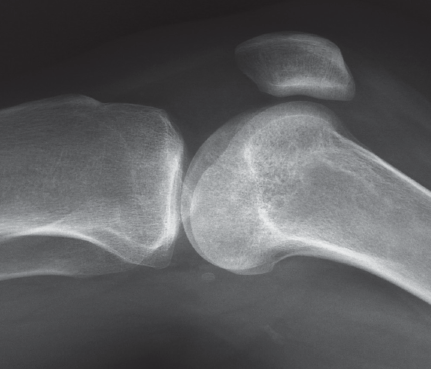

Physical exam reveals mild distress related to her knee pain. Though patient is mildly obese, all of her vital signs are within normal limits. The physical exam of the left knee demonstrates slightly reduced active range of motion related to pain. Passive range of motion is full. No specific position makes the pain better or worse. Stress tests to assess the ligaments are negative. Two views of the left knee are obtained in further investigation (Figures 1 and 2). The frontal and lateral conventional radiographs of the knee demonstrate punctate areas of sclerosis in the distal femur and proximal tibia. On the lateral view there is no evidence of a joint effusion.

Figure 1. A frontal radiograph of the knee demonstrates punctate areas of sclerosis

Figure 2. A lateral radiograph of the knee demonstrates punctate areas of sclerosis and the absence of a joint effusion.